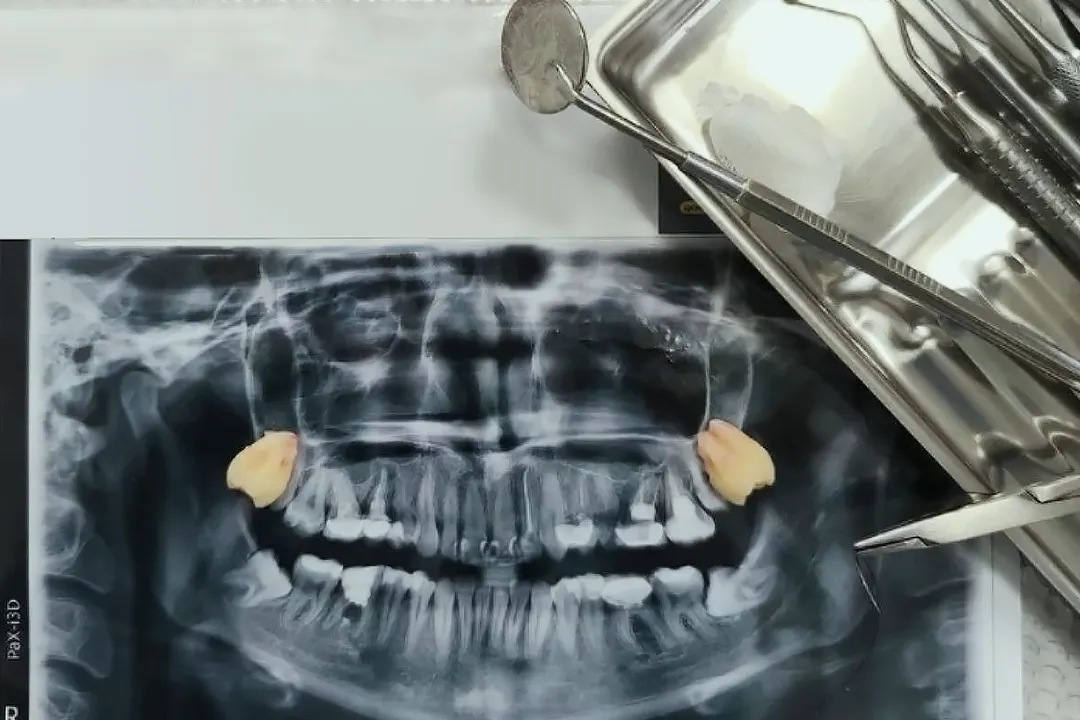

Лікар проводить огляд, виконує рентген або КТ для оцінки коренів, кісткової тканини та стану оточуючих структур.